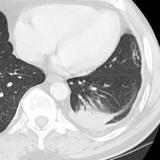

Rounded atelectasis case 2

Date: 03/28/2009

Views: 3011